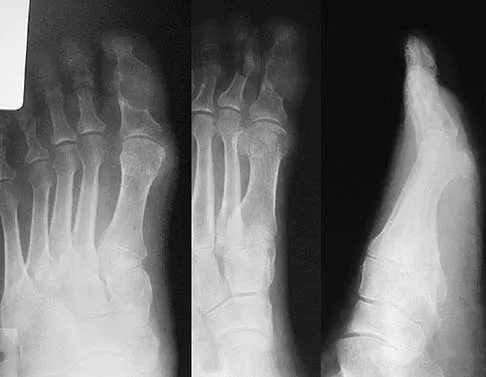

An active 47-year-old woman with rheumatoid arthritis reports forefoot pain and deformity and has difficulty with shoe wear. Examination reveals hallux valgus and claw toes. A radiograph is shown in Figure 10. What is the most appropriate surgical treatment?

Explanation

Rheumatoid arthritis commonly affects the metatarsophalangeal joints, which become destabilized with time resulting in hallux valgus and dislocated lesser claw toes. The result is metatarsalgia as the dislocated claw toes "pull" the fat pad distally. Severe hallux valgus reduces first ray load, which compounds the metatarsalgia because the load is transferred to the lesser metatarsal heads. First metatarsophalangeal arthrodesis restores weight bearing medially and corrects the painful bunion. Metatarsal head resection slackens the toe tendons to allow correction of the claw toes by whatever means necessary and decreases plantar load over the forefoot. Rheumatoid arthritis in the first metatarsophalangeal joint will continue to progress if osteotomies or a Lapidus procedure are performed. Keller resection arthroplasty increases transfer metatarsalgia and reduces push-off power during gait. Flexor-to-extensor tendon transfer of the lesser toes does not address the metatarsalgia and does not correct the dislocation of the metatarsophalangeal joint. Coughlin MJ: Arthritides, in Coughlin MJ, Mann RA (eds): Surgery of the Foot and Ankle, ed 7. St Louis, MO, Mosby, 1999, p 572.